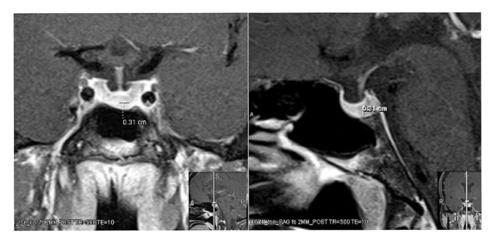

54 year old menopausal lady (gravida 10, para 7, abortions 3) with history of Chronic Obstructive Pulmonary Disease(COPD) and multiple back surgeries presented for endocrine evaluation for elevated serum hCG levels found incidentally during a preoperative evaluation for back surgery. She reported intermittent nausea and vomiting, similar to her morning sickness experienced when she was pregnant along with headaches and weight loss of 20 lbs over 4 years. She arrived at menopause 7 years prior to her current presentation and did not report irregular bleeding, visual disturbances or vasomotor symptoms of menopause since then. Physical exam revealed a BMI of 21 with chronic left lower extremity weakness. She denied using hCG supplements for weight management. She worked on a farm and handled animals for about 20 years. She also had detectable serum hCG 4 years ago which was not investigated further. Lab investigations revealed 6 separate measurements of persistently elevated quantitative hCG ranging from 15 to 20mIU/ml (normal: <10mIU/ml in menopause), indeterminate qualitative hCG assays and negative urine hCG tests over period of 10 months. Pelvic ultrasound showed normal uterus with 3mm endometrial stripe and no evidence of ovarian or uterine mass or free fluid in the cull de sac. Antibody interference by HAMA (human anti-mouse monoclonal antibody) was determined to be negative. Also, hCG was measured by two other different assays including Beckman DxI and Siemens Centaur platform were 26 mIU/ml and 18.6 mIU/ml respectively. With persistently elevated hCG on several occasions also verified through a different laboratory assay with no evidence of gestational trophoblastic disease pointed towards pituitary gland as the potential source. Enhanced MRI of the pituitary (Figure 1) showed a 3mm hypo enhancing focus concerning for pituitary adenoma. The complete endocrine work up revealed normal cortisol, thyroid function tests, prolactin, IGF-1, estradiol and elevated FSH of 146.6 mIU/ml (Menopause:23.0-116.3mIU/ml) and LH of 85.1 mIU/ml (Menopause: 10.0-54.7mIU/ml) consistent with menopause. Hormonal replacement therapy with 1 mg estradiol and 100 micrograms of micronized progesterone was initiated to potentially switch off the hCG secretion of pituitary origin, however patient could not tolerate it more than 3 days due to mood swings. She denied another trial. At ten months of follow up; she continues to have mild symptoms of nausea.

Figure 1 Enhanced MRI of the Pituitary showing a 3 mm Pituitary Adenoma.